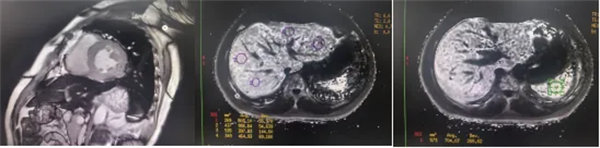

在常規心臟MRI檢查中,醫學影像科發現患者心肌異常表現,考慮鐵過載性心肌病,為明確診斷要進一步加做鐵定量技術,加掃T2 mapping序列。CMR鐵定量技術是目前評估心肌鐵含量的“金標準”,能夠快速、無創、精準量化心肌內鐵沉積程度,檢查結果提示患者局部心肌T2*值顯著低于正常范圍,符合鐵過載性心肌病的診斷標準。

CMR是目前唯一能定量檢測組織鐵負荷的無創影像學手段,主要依賴其 T2*mapping技術測量的T2*弛豫時間(T2*值)間接量化組織鐵含量。當CMR檢測出心肌T2*<20 ms時,初步診斷心肌鐵過載,T2*值<10-15ms時,提示心功能受損風險顯著增加。T2值越低,鐵沉積越嚴重。目前T2*mapping技術檢測T2*已作為臨床診斷肝臟、心肌鐵過載的首選無創檢查,也被用作隨訪工具評估疾病進展和療效。

基底部、中間部及心尖部 局部心肌T2*值明顯減低T2* 10-20/s, 部分小于10/s

心肌信號局部減低 呈現“黑色心肌”表現,這是由于鐵沉積導致局部磁場不均勻,引起信號丟失(失相位)。

肝臟和脾臟信號改變 矢狀位梯度回波定位圖像可顯示肝臟和脾臟信號降低,提示肝脾鐵沉積,T2*>6.3及R2*>160/s表現中度鐵過載。